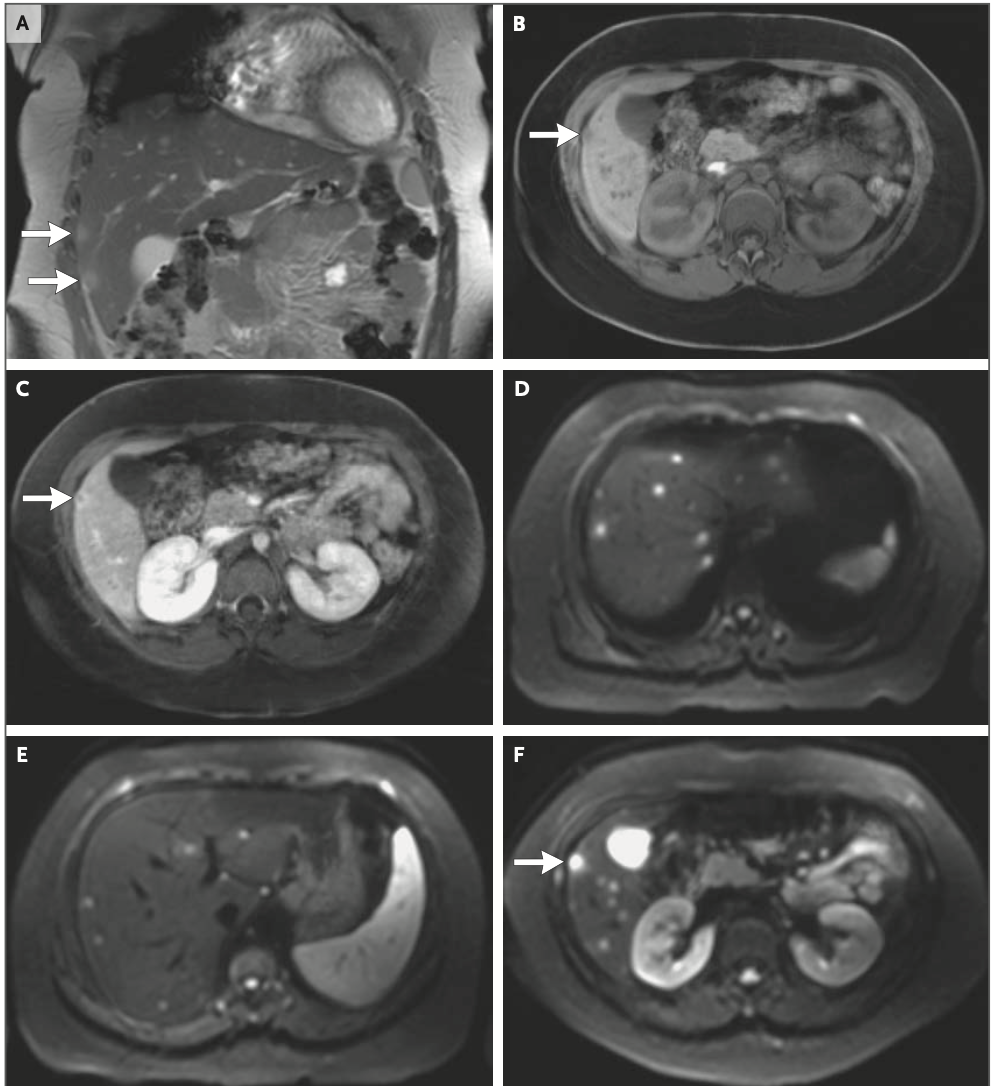

11歳女児の7日程度の経過で認めた胸痛、多発骨病変(胸骨、右上腕骨頭)、多発肝病変の症例です。既往はアトピー性皮膚炎、MRSA皮膚感染症があり、子猫を飼い始めたという生活歴があったようです。血液検査は炎症反応以外はパッとしないという感じです。下に論文内の画像所見を貼っています。

全身疾患となった場合、バルトネラは肝臓、骨、眼、中枢疾患などに播種性病変を形成し、不明熱の原因疾患とされる。下肢の骨や脊椎病変が多いが、あらゆる腸管骨や胸骨も病変を形成しうる。肝臓や脾臓に多発微小膿瘍を形成することがあり、本症例と合致する。